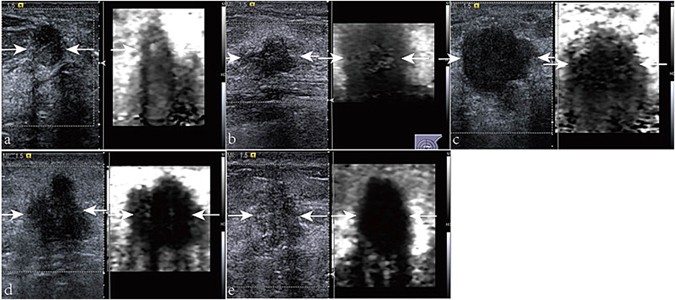

Figure 3

Virtual Touch tissue imaging elasticity scores of the lesions (arrows): (a) score 2; (b) score 3; (c) score 4; (d) score 5; and (e) score 6.